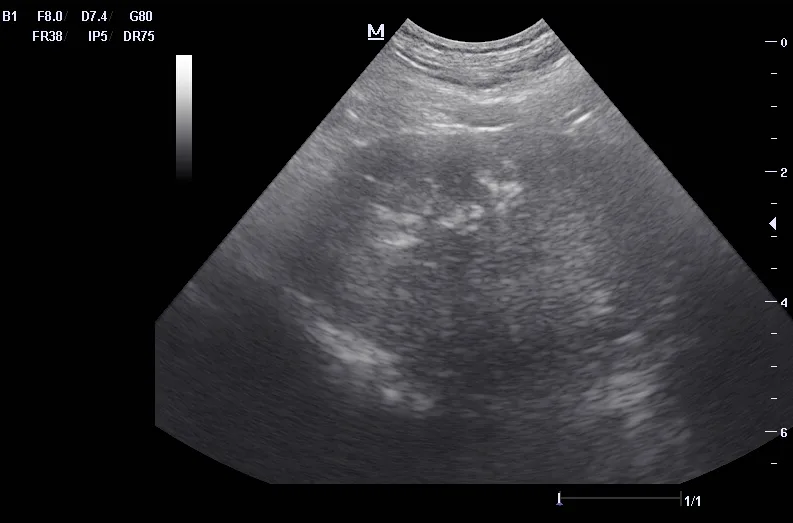

Ultrasound can be useful in evaluating the size, contour, and internal architecture of the prostate. A normal prostate appears homogeneous (Figure 1). The prostate becomes heteroechoic as a result of inflammation, hyperplasia, and neoplasia (Figure 2). The prostatic parenchyma can be focally or diffusely hypoechoic in cases of acute prostatitis or prostatic abscessation (Figure 3), as well as hyperechoic in cases of chronic prostatitis (Figure 4).

Ultrasound image of a normal canine prostate.

FIGURE 1

Normal prostate with a homogeneous appearance